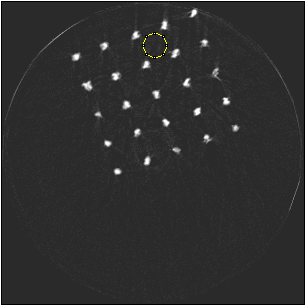

Figure 3 shows a single slice spectral reconstruction of the Ti phantom. The cupping effect is prominent in the low energy range and decreases in the high energy acquisitions. The thresholds were determined to provide a trade-off between reduced photon noise and cupping effect. The spectral images for the energy ranges 55 to 80 keV and 62 to 80 keV exhibit reduced cupping effect while the 15 to 80 keV reconstruction has low quantum noise and shows good contrast in non-metal regions. In figure 4, a horizontal line profile passing through the origin of the metal cylinder shows cupping effect in the different energy ranges. Without the use of any hardware filters, a significant reduction in the cupping effect is noticeable in figure 4c. The reconstruction corresponding to the energy range from 62 to 80 keV suffers from severe photon limitation giving rise to statistical noise. Any significant increase in tube current and/or exposure time for this scan resulted in detector saturation in non-metal regions.